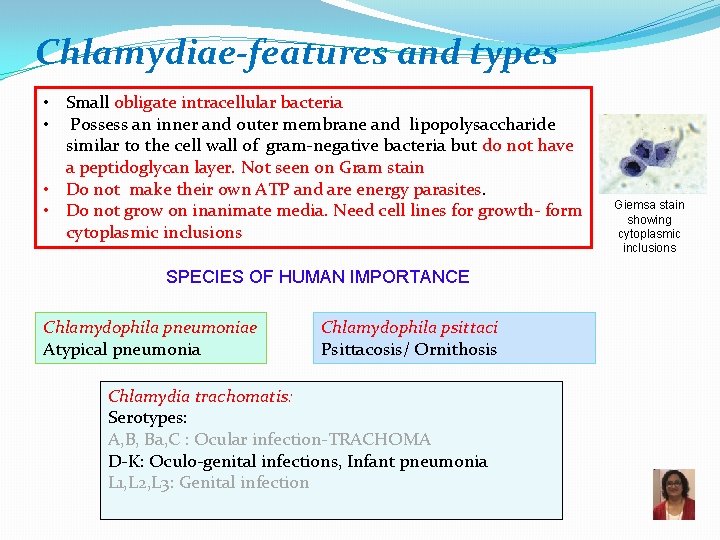

Chlamydiae-features and types • Small obligate intracellular bacteria • Possess an inner and outer membrane and lipopolysaccharide similar to the cell wall of gram-negative bacteria but do not have a peptidoglycan layer. Not seen on Gram stain • Do not make their own ATP and are energy parasites. • Do not grow on inanimate media. Need cell lines for growth- form cytoplasmic inclusions SPECIES OF HUMAN IMPORTANCE Chlamydophila pneumoniae Atypical pneumonia Chlamydophila psittaci Psittacosis/ Ornithosis Chlamydia trachomatis: Serotypes: A, B, Ba, C : Ocular infection-TRACHOMA D-K: Oculo-genital infections, Infant pneumonia L 1, L 2, L 3: Genital infection Giemsa stain showing cytoplasmic inclusions